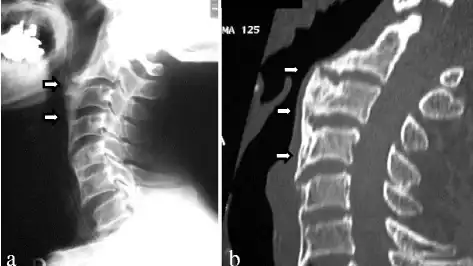

a) Recurrent ossification of anterior longitudinal ligament with anterior osteophytes arrows was present from C2 to C6 b) computed tomographic images of the cervical spine -